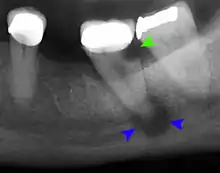

Decay (green) with apical abscess (blue)

Gutta-percha point indicating abscess origin